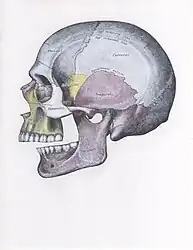

Anatomy

The joint involved with jaw dislocation is the temporomandibular joint (TMJ). This joint is located where the mandibular condyles and the temporal bone meet.[4][6] Membranes that surround the bones help during the hinging and gliding of jaw movement. For the mouth to close it requires the following muscles: the masseter, temporalis, and medial pterygoid muscle. For the jaw to open it requires the lateral pterygoid muscle.[4]